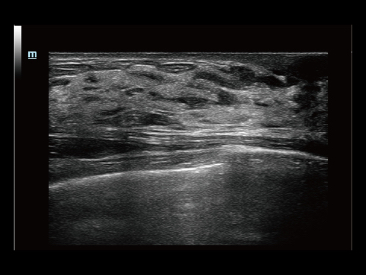

Adem├Īs de la calidad de imagen de primer nivel, Resona?7 tambi├®n mejora las capacidades de investigaci├│n cl├Łnica con el revolucionario V?Flow para la evaluaci├│n hemodin├Īmica vascular y con la adquisici├│n de planos m├Īs inteligente a partir de conjuntos de datos 3D para el diagn├│stico del SNC fetal. Al combinar el funcionamiento multit├Īctil basado en gestos m├Īs intuitivo y todas las caracter├Łsticas cl├Łnicas esenciales, Resona?7 realmente lidera las novedades en innovaci├│n de ecograf├Łas.